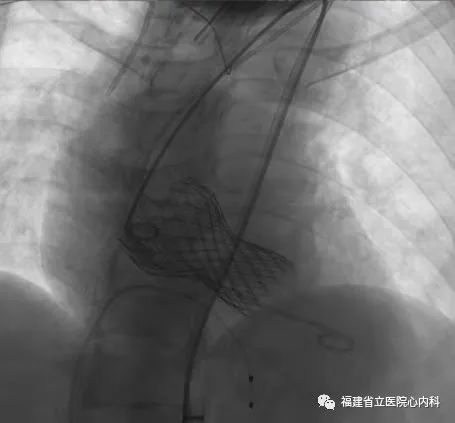

该病例是一个单纯重度主动脉瓣返流患者,主动脉瓣上没有稳定的锚定结构,通过依靠瓣环及左室流出道,瓣膜移位及瓣周漏风险大,手术难度极大,术者通过CT仔细制定了手术策略及各种预案,最终顺利植入29号瓣膜,术后无返流及瓣周漏,手术效果佳。

瓣环

窦部

植入L29瓣膜